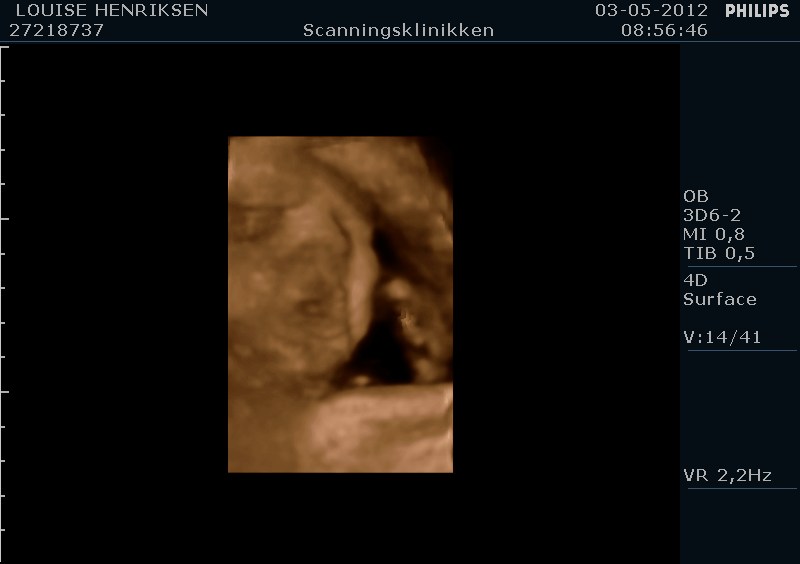

I dag skulle manden overraskes med en 4 d scanning.... og hans far var også med det var også en overraskelse, samt den lille prins....han fik bind for øjene og vi kørte mod scanning klinikken.... vi fik nogle gode sekvenser af bettemanden.. men han fylder en del derinde nu, så billederne blev ikke voldsomt gode.. men nogle fik vi dag...jeg skulle i morgen være 32 fulde uger.. mne scanningen i dag vidste34+4 dage yiarks.... jeg skal til at være færdig med den bachelor..... han vejede efter målene 1871 gram.....

så han var en fin basse...